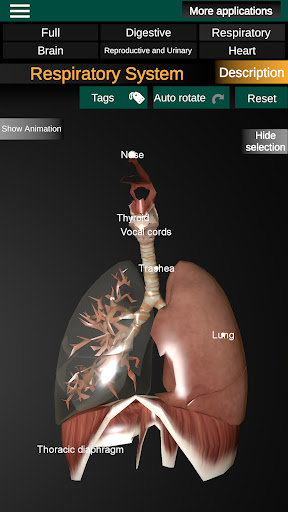

* Дихальна система, яка включає трахею, бронхи, легені та анімацію цієї системи.